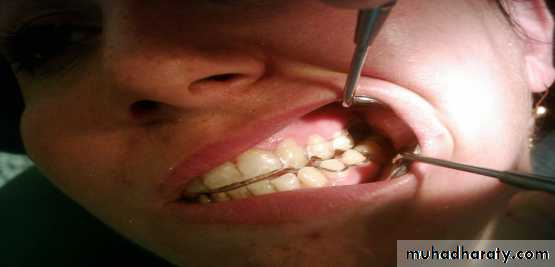

* occlussal splint therapy

It is a removable appliance that fits over the occlusal & incisal surface of the teeth in one arch creating precise occlusal contact with the teeth of the opposing arch ,

Bite Plate

Is one of the reversible modality in treatment of temporomandibular joint disorders.There are five general features common to all splints that may be responsible for decreasing muscle activity and symptoms:

TYPES OF OCCLUSAL SPLINTS:

• anterior repositioning splint

• A interocclusal appliance that encourages the mandible to assume a more anterior position .